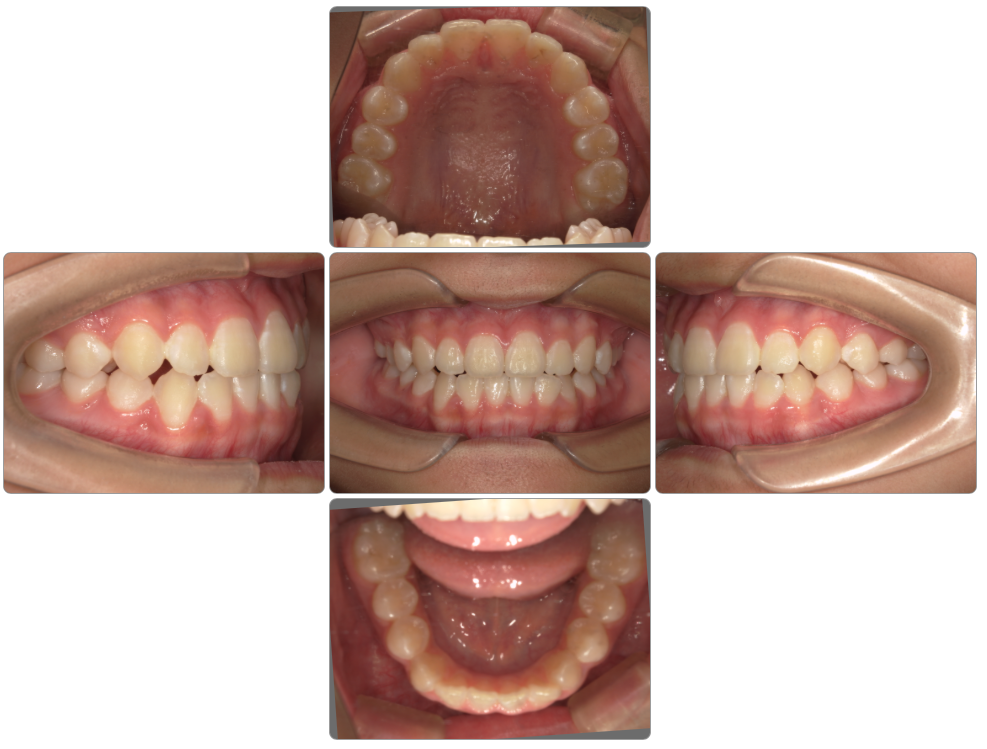

上顎前突の治療例

Before

after

| 初診時 | 8歳1か月 |

| 治療期間 | 2年2ヵ月 |

| 費用 | ¥550,000 調整料・¥5,500/月 |

| 使用装置 | マイオブレイス・BWS |

| リスクと副作用 | |

| 原因と考察 | 頚椎成長が足りないために下顎骨の高さが育っていません。このことが口腔の高さが不足しています。マイオブレイスを使用していると厚みがある分下顎骨の高さがますのでこのように過蓋咬合が改善に導かれます。ただ全身の問題で考えると頚椎成長を促すような生活指導は原因除去という点では欠かせません。 |